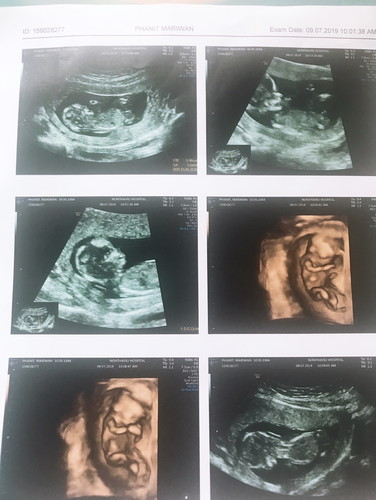

เพศหญิงหรือเพศชายคะ

รบกวน คุณแม่ๆช่วยแชร์ประสบการณ์จากรูปที่เห็นคะว่าเพศหญิงหรือชายคะ

บอกได้แค่บ้านนี้ท้องแหลมผู้ชายคะ แต่ไม่เห็นมีรูปที่แม่พูดถึงเลย

ผู้ชายไหมแม่ รูปที่2ต่อจากรูปแรกน้องมีอะไรโผล่ขึ้นมา😊